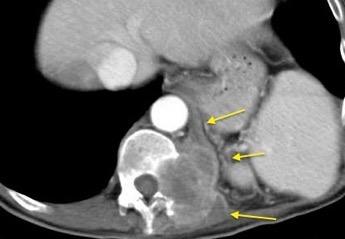

T. mixto de células germinales del testículo izquierdo

Nódulos pulmonares múltiples. (flechas verdes). Masas paratraqueales. (flechas amarillas). Dudoso ensanchamiento retrocrural (flechas negras). sigue….

Ttawfik A et al. Trans-diaphragmatic Pathologies: Anatomical Background and Spread of Disease on cross-sectional Imaging. Current Problems in Diagnostic Radiology. 2021.

T. mixto de células germinales del testículo

izquierdo Metástasis pulmonares. (flechas verdes). Ganglios paratraqueales. (flechas amarillas). Ganglios retroperitoneales (flechas negras)

Tawfik A et al. Trans-diaphragmatic Pathologies: Anatomical Background and Spread of Disease on cross-sectional Imaging. Current Problems in Diagnostic Radiology. 2021.